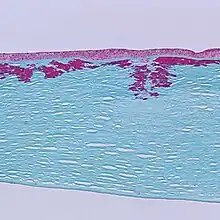

| Reis-Bücklers corneal dystrophy. Reticular opacity in the superficial cornea | |

Patients with Reis-Bücklers dystrophy develop a reticular pattern of cloudiness in the cornea. This cloudiness, or opacity, usually appears in both eyes (bilaterally) in the upper cornea by 4 or 5 years of age. The opacity elevates the corneal epithelium, eventually leading to corneal erosions that prompt attacks of ocular hyperemia, pain, and photophobia. These recurrent painful corneal epithelial erosions often begin as early as 1 year of age.[1]

With time, the corneal changes progress into opacities in Bowman's membrane, which gradually becomes more irregular and more dense.[1] Significant vision loss may occur.[2] However, vascularization of the cornea is not present.[2]